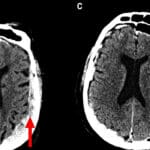

Skeniranje mozga

Prvo skeniranje umirućeg mozga otkriva posljednje trenutke

mozak